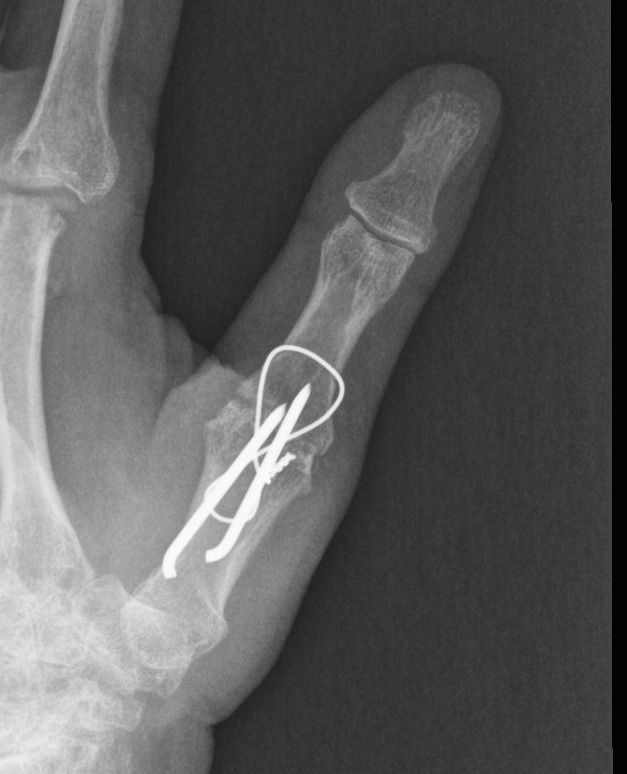

Type IV - Gamekeepers

- due to MCPJ synovitis

- stretches UCL

- either synovectomy / UCL reconstruction

- or fusion